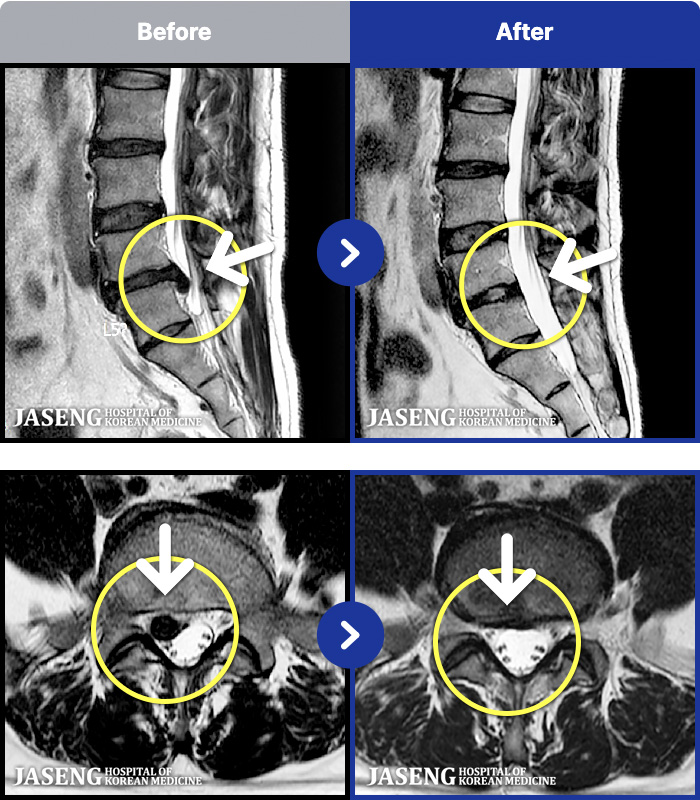

MRI ġ

191 MRI ũ ʸ Ȯϼ.

[õ] 19.02.09~20.07.18

ȯںп Ǹ ǿ ԿǾ, ο ġ ۿ Ƿ ġḦ Ͻñ ٶϴ.